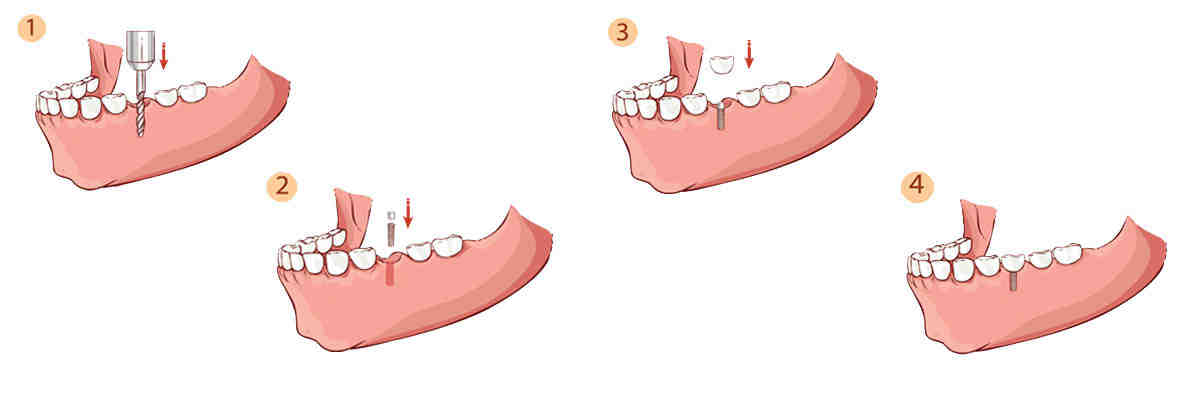

How long does a dental implant procedure take?

Medical Treatment The dentist will insert a titanium plant into your bone, right under the gums. This process usually takes about 1-2 hours for each installation. After this procedure is completed, most dentists will wait about 3 months before the final use of the tooth.